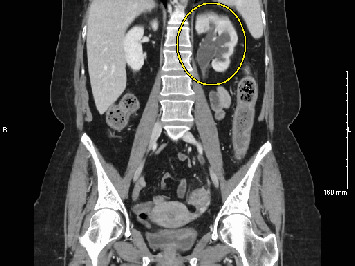

尿脓毒症是一种源自泌尿道的严重感染,可能危及生命。我们报告了一位56岁的女性患者,她在15天内两次出现尿脓毒症,每次发作都发生在支架移除后不久。输尿管镜下支架置入治疗左侧远端输尿管12毫米结石。尽管在影像学检查未发现结石残留后才取出支架,但不久后脓毒症发生,导致再次输尿管镜检查和支架置入。在第二次支架移除之前,影像学再次证实没有结石存在,但在第二次支架移除后,她再次出现败血症。两例败血症住院期间的进一步影像学检查显示结石碎片和肾积水,这在办公室评估中被遗漏。这个病例强调需要更有效的成像技术来检测残留的结石。输尿管镜下输尿管结石治疗后放置支架的决定也应仔细考虑,即使是低风险患者,以减少感染风险。

Urosepsis, a severe infection originating from the urinary tract, can be life-threatening. We present the case of a 56-year-old female who developed urosepsis twice within 15 days, each episode occurring shortly after stent removal. Ureteroscopy with stent placement was initially performed to treat a 12-mm stone in the distal left ureter. Although the stent was removed only after imaging showed no residual stones, sepsis developed shortly after, leading to another ureteroscopy and stent placement. Before the removal of the second stent, imaging again confirmed no stones were present, yet she experienced sepsis once more following the second stent removal. Further imaging studies during hospital admission for both episodes of sepsis revealed stone fragments and hydronephrosis which were missed during office evaluations. This case highlights the need for more effective imaging techniques to detect residual stones. The decision to place a stent after ureteroscopy for ureteral stone treatment should also be carefully considered, even for low-risk patients, to reduce infection risk.